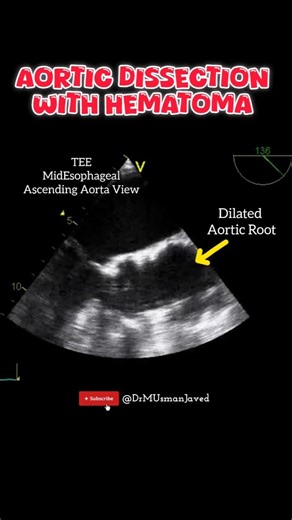

Aortic Dissection Explained